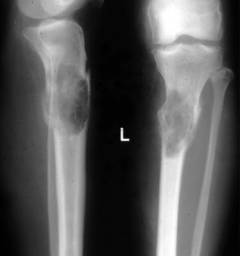

- Рентгенография костей метод рентгенологического исследования костей. Цель выявить участки поражения костей и подтвердить диагноз «миеломная болезнь». Для того чтобы получить полное представление о степени поражения делают снимки с передней и боковой проекции.

Изменения на рентгене при миеломной болезни:

- признаки очагового или диффузного остеопороза (снижение плотности костной ткани)

- плечевые кости – отверстия в виде сот или «мыльных пузырей»

- Спиральная компьютерная томография (СКТ) – исследование, основанное на серии рентгеновских снимков, сделанных с разных ракурсов. На их основе компьютер составляет послойные «срезы» человеческого тела.

- очаги разрушения кости

- опухоли мягких тканей

- деформация костей и позвонков